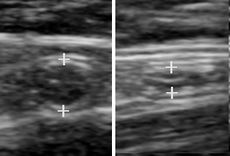

Compression ultrasonography is when the probe is pressed against the skin. This can bring the target structure closer to the probe, increasing spatial resolution of it. Comparison of the shape of the target structure before and after compression can aid in diagnosis.

Panoramic ultrasonography of a proximal biceps tendon rupture. Top image shows the contralateral normal side, and lower image shows a retracted muscle, with a hematoma filling out the proximal space.